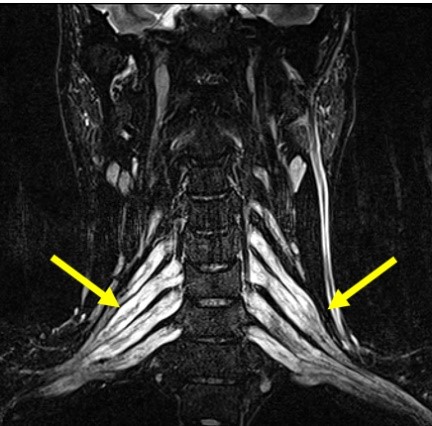

多発性硬化症(MS) 慢性炎症性脱髄性多発神経炎(CIDP)

脱髄性病変 T2協調像 腕神経叢のびまん性の腫大 STIR画像